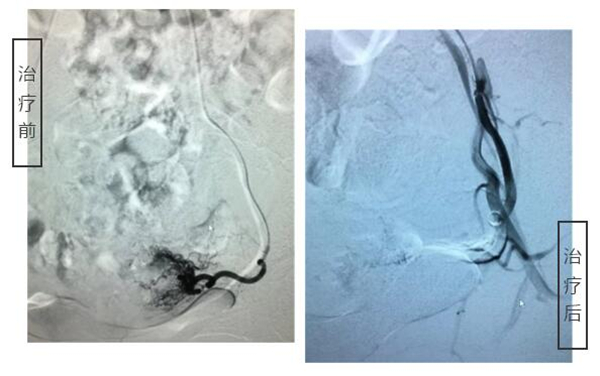

3月13日下午,由血管外科主任何永健主刀,在局麻的状态下,为邰女士实施了介入治疗。整个过程30分钟左右即告顺利完成,患者全程是清醒的,术后即可正常吃喝活动,1-2天便可出院。

左侧子宫动脉

右侧子宫动脉